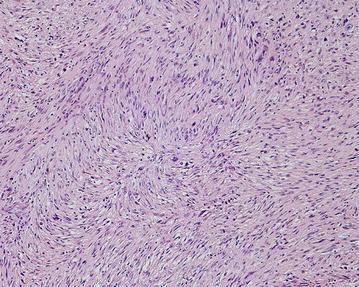

The authors describe clinical and radiologic features, histologic appearance, and treatment of osteogenic osteosarcoma located in the proximal femoral diaphysis associated with an unstable femoral prosthesis following THA in a 65-year-old male patient. The patient with HLA-B27 positive ankylosing spondylitis underwent arthroplasty 15 years ago.